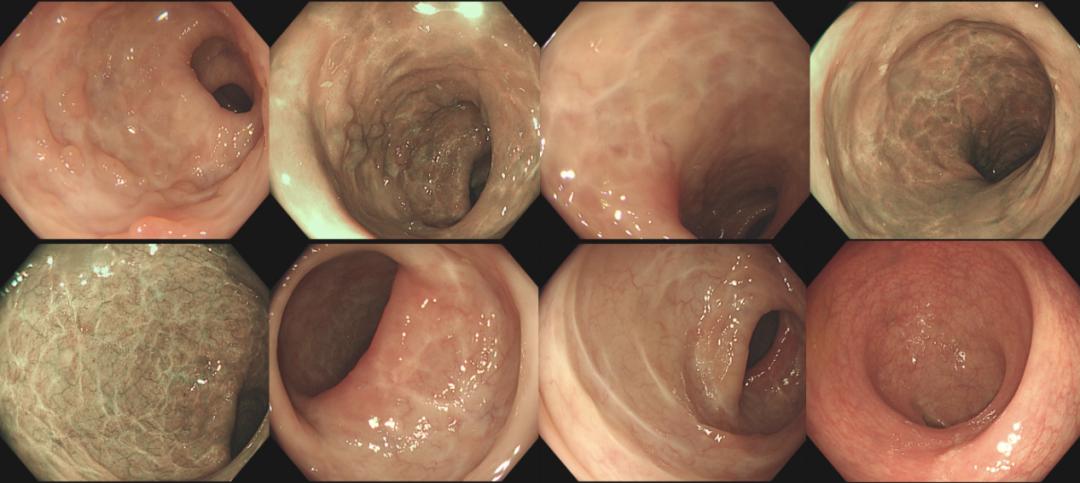

20220110肠镜检查:插镜至回末,距肛缘28~10cm可见四壁黏膜鹅卵石样表现、散在溃疡、小片状糜烂、可见新鲜血迹及脓性分泌物,10cm至肛缘四壁黏膜散在红斑、充血水肿明显(图1)。诊断为UC、E2、活动期、乙状结肠Mayo 3分、直肠Mayo 2分。

图1 入院时肠镜检查图

20220704 肠镜检查(图7):提示粘膜愈合

图7 2022年7月4日肠镜复查